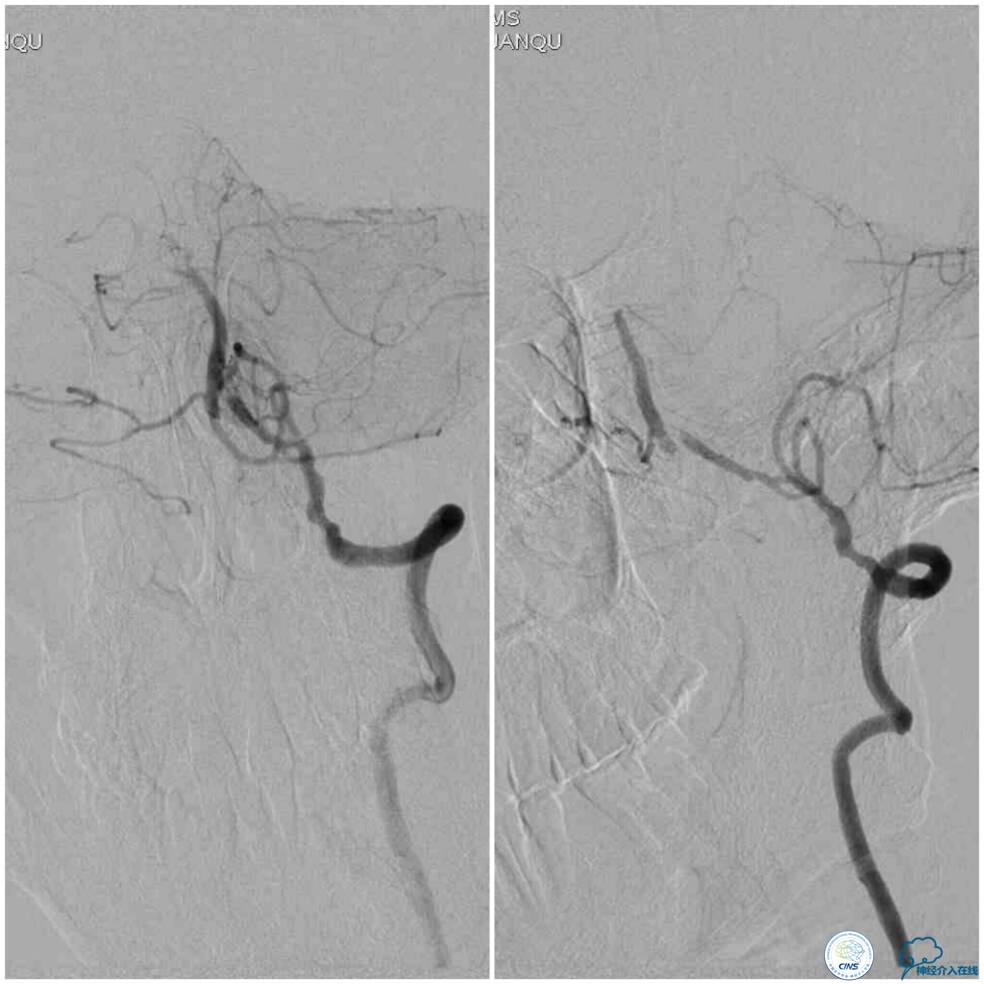

血栓弹力图检查:AA抑制率98.2%、ADP抑制率47.7%。颅内CTA及后循环CT灌注检查提示:右椎动脉V4段未见显影,左椎动脉与基底动脉汇合处重度狭窄,右椎动脉V4段在汇合点以下有显影(图5);双侧小脑半球低灌注,右侧为著(图6)。

图5

图6